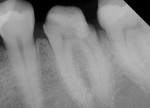

Radiographic interpretation shows the close approximation of an asymptomatic pulp (Figure 4). TheraCal LC was placed onto moist dentin in up to 1-mm increments and immediately light-cured. ALL-BOND SE® (BISCO) was subsequently placed to bond CORE-FLO™ DC (BISCO) as a base/core (Figure 5). Both TheraCal LC and CORE-FLO DC are radiopaque, allowing these materials to be easily identified on radiographs (Figure 6).